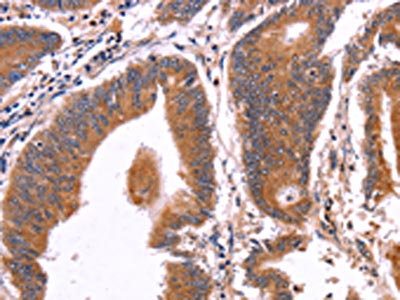

The image on the left is immunohistochemistry of paraffin-embedded Human thyroid cancer tissue using CSB-PA795553(CRISP3 Antibody) at dilution 1/50, on the right is treated with fusion protein. (Original magnification: ×200)

The image on the left is immunohistochemistry of paraffin-embedded Human colon cancer tissue using CSB-PA795553(CRISP3 Antibody) at dilution 1/50, on the right is treated with fusion protein. (Original magnification: ×200)